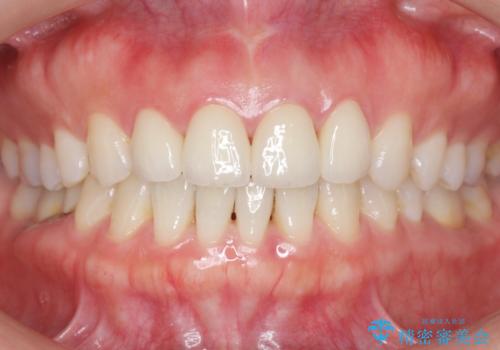

自然な仕上がりに大変喜んで頂けました。

単冠かつ適合の良いクラウンにより清掃性が良くなり、歯茎の腫れ・出血もなくなりました。

天然歯と見紛うほど自然なセラミッククラウンは、熟練した技工士さんの技術の賜物です。

クラウンの種類:ジルコニアオールセラミッククラウン エクセレント